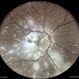

- A 45-year-old female presented with complaints of gradual loss of vision before 3 months and when reached to hospital had this picture.